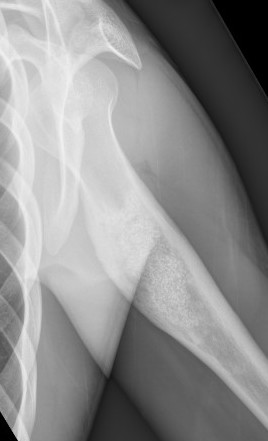

X-ray

Well-defined lucency

- thin sclerotic rim

- usually central

- thinned cortex with slight expansion

- thin internal septa

- can be multi-loculated

Fallen-Leaf (AKA fallen-fragment)

- with pathological fracture

- indicates that the lesion has no matrix and is fluid filled

Fallen leaf sign